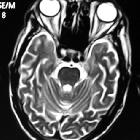

Ectopic

internal carotid artery presenting as an oropharyngeal mass. Magnetic Resolution Angiography after gadolinium administration shows the helicoids-ectopic course of the right ICA, immediately after the carotid bulb. Notice also, the significant stenosis of the controlateral left ICA.